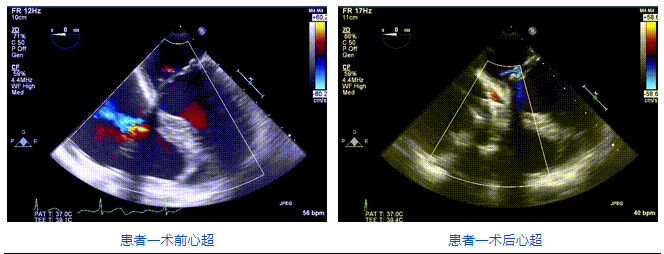

2021年12月24日,復(fù)旦大學(xué)附屬中山醫(yī)院葛均波院士團(tuán)隊成功應(yīng)用LuX-Valve Plus為一例極重度三尖瓣反流(TR)合并房顫、房缺的患者完成了經(jīng)血管三尖瓣置換術(shù),這是在前基礎(chǔ)上,本周完成的第三例經(jīng)血管三尖瓣置換手術(shù),葛均波院士、周達(dá)新教授等與心外科魏來教授、賴顥教授,心超室的潘翠珍教授、李偉教授及麻醉科的郭克芳教授共同完成了本周手術(shù),均獲得圓滿成功!患者術(shù)后超聲顯示無TR,臨床癥狀明顯改善。本周手術(shù)的成功也為LuX-Valve Plus救治性臨床研究添上了濃墨重彩的一筆。

本周三例接受LuX-Valve Plus經(jīng)血管三尖瓣置換術(shù)的患者中,第一例患者為冠狀動脈旁路移植術(shù)+Bentall+二尖瓣成形術(shù)后;第二例患者為永久起搏器植入術(shù)后,存在跨三尖瓣導(dǎo)線;第三例患者合并房顫、房缺及左心耳封堵術(shù)后。

三例患者入院后,葛均波院士團(tuán)隊周達(dá)新教授、潘文志教授、張源博士、陳莎莎博士及心超室的潘翠珍教授、李偉教授對患者的情況進(jìn)行詳細(xì)評估和討論,最終決定為三例患者選擇LuX-Valve Plus40mm、50mm和50mm型號的瓣膜進(jìn)行手術(shù)治療。手術(shù)后即刻拔除氣管插管,術(shù)后患者三尖瓣反流癥狀得到顯著改善,復(fù)查心超結(jié)果顯示人工三尖瓣瓣膜支架固定穩(wěn)定,瓣葉關(guān)閉形態(tài)未見異常,未見明顯反流。